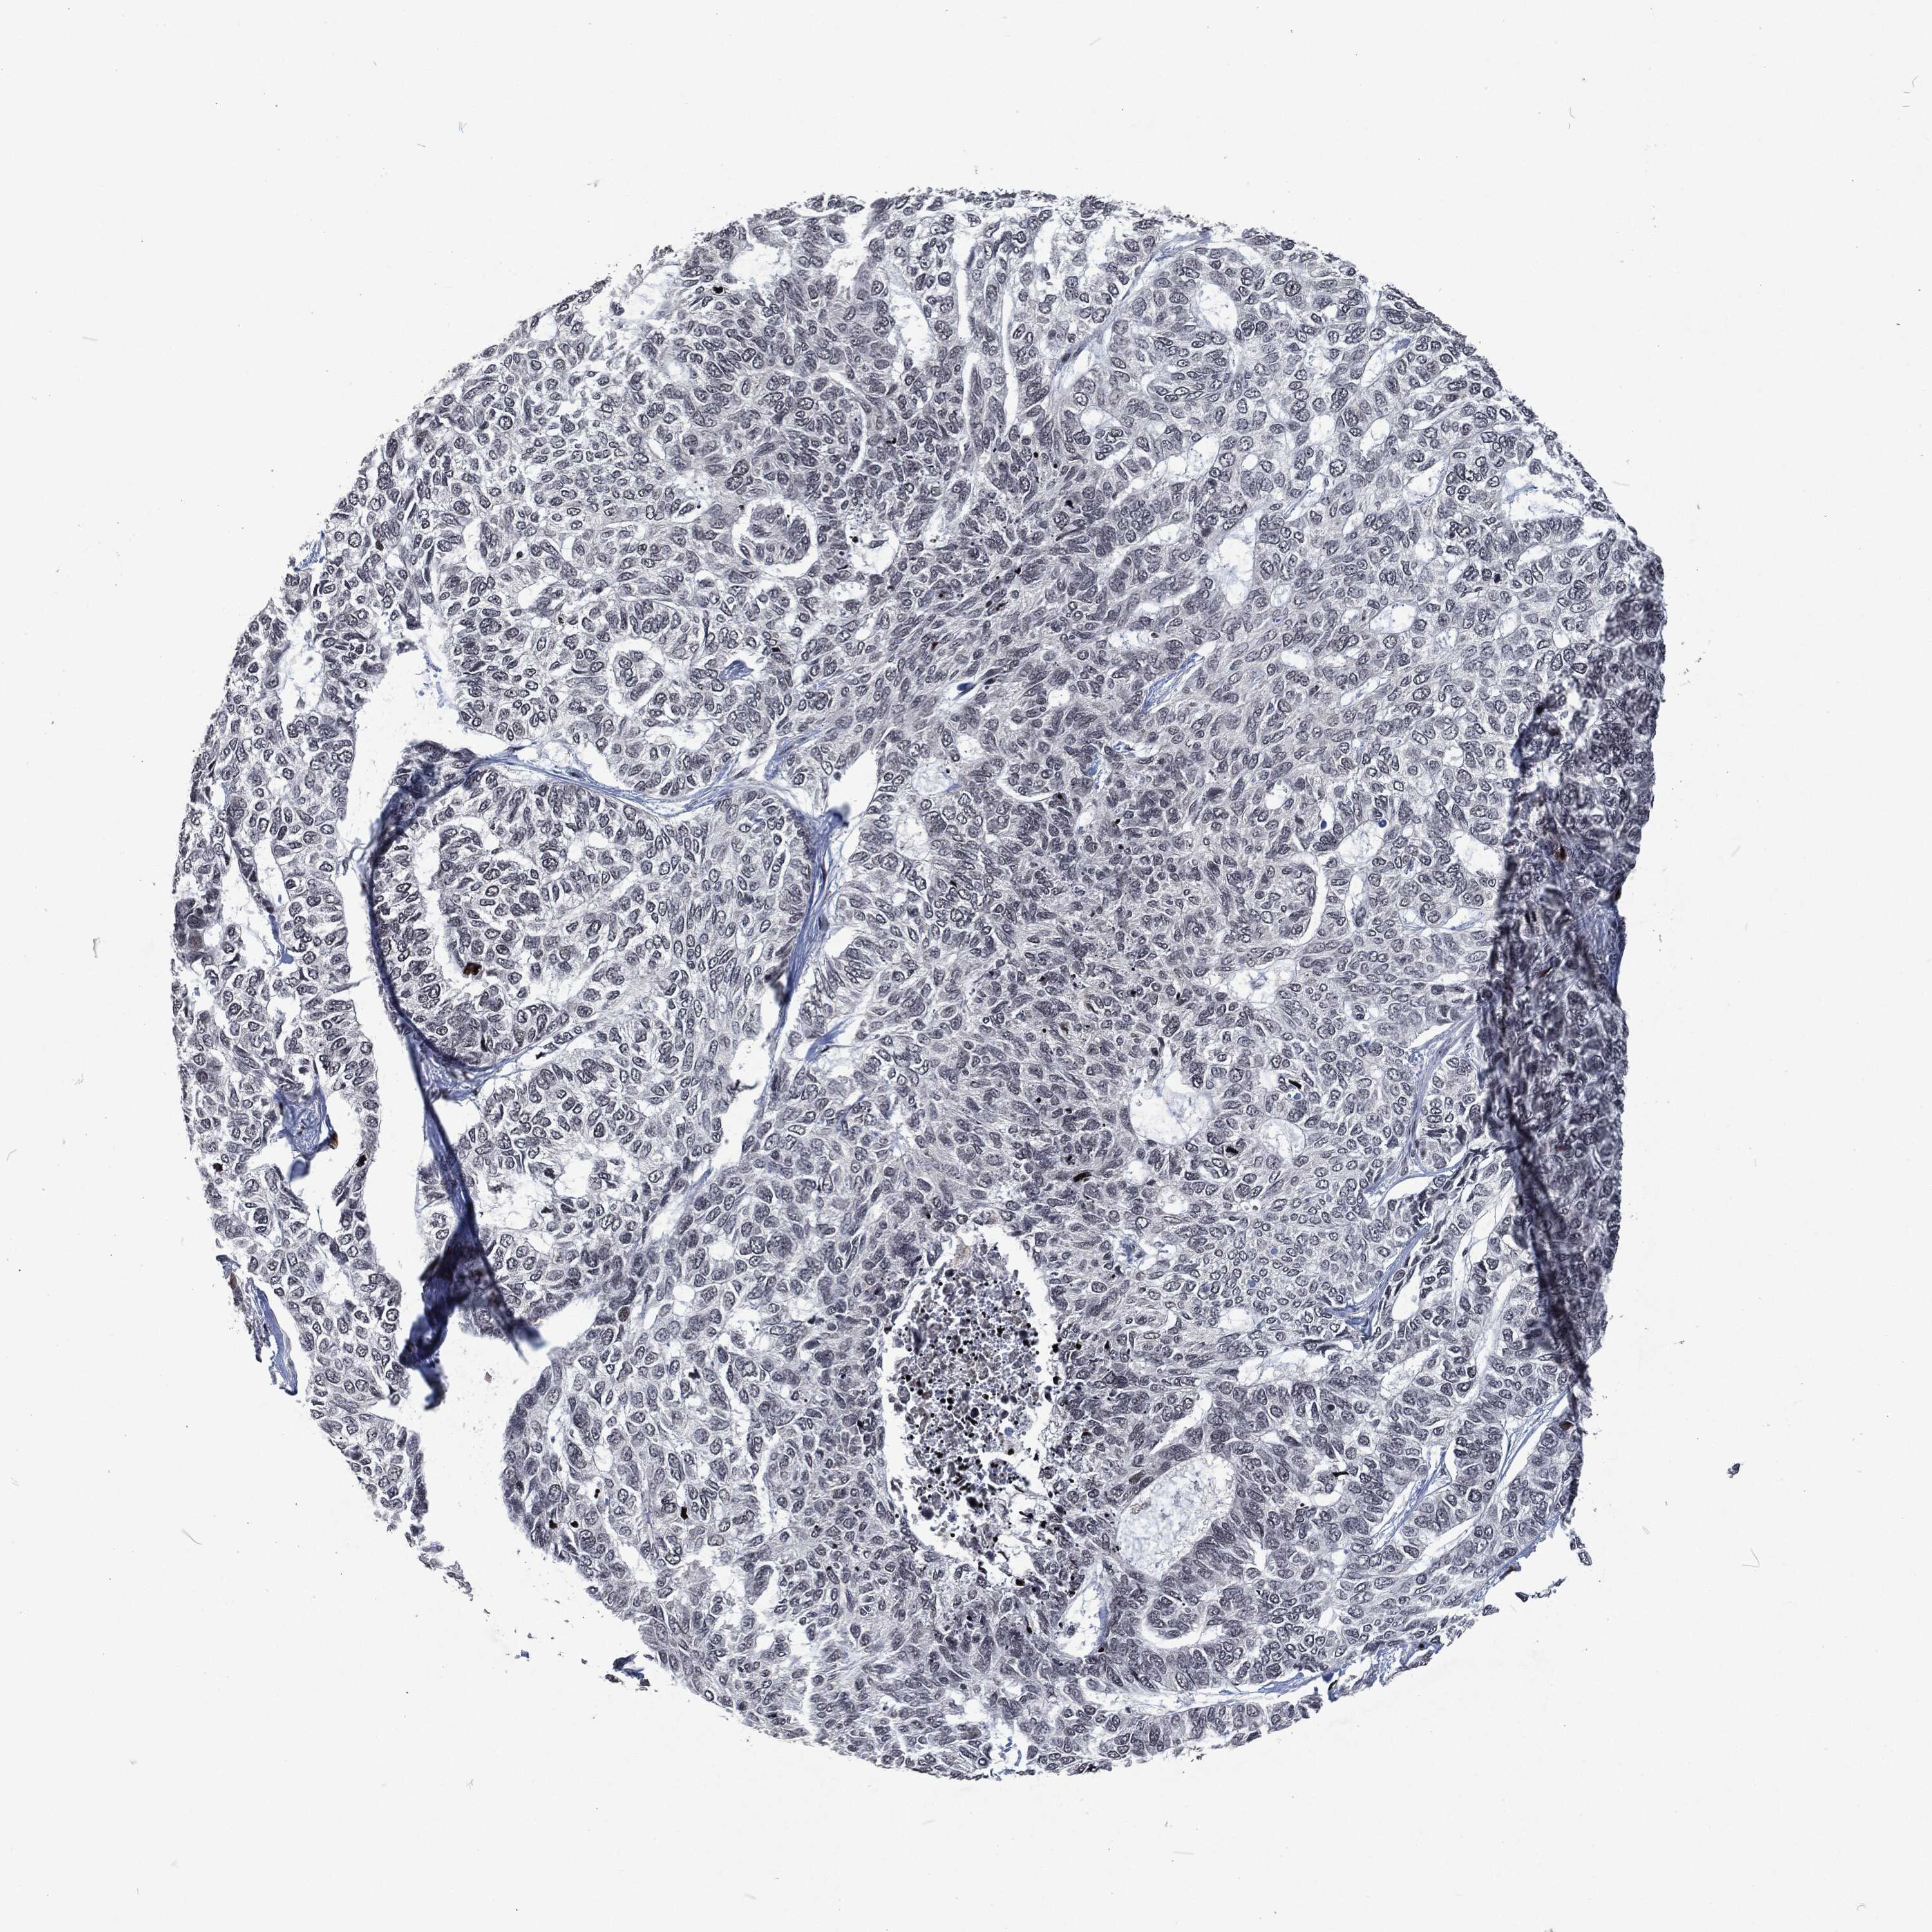

CANCER SKIN CANCER Show tissue menu

SKIN CANCER - Protein expressioni

A mouse-over function shows sample information and annotation data. Click on an image to view it in a full screen mode. Samples can be filtered based on level of antibody staining by selecting one or several of the following categories: high, medium, low and not detected. The assay and annotation is described here.

Each image is clickable and will lead to virtual microscopy that enables deeper exploration of all samples and also displays staining intensity scores, fraction scores and subcellular localization as well as patient and tissue information for each sample.

Squamous cell carcinoma, NOS